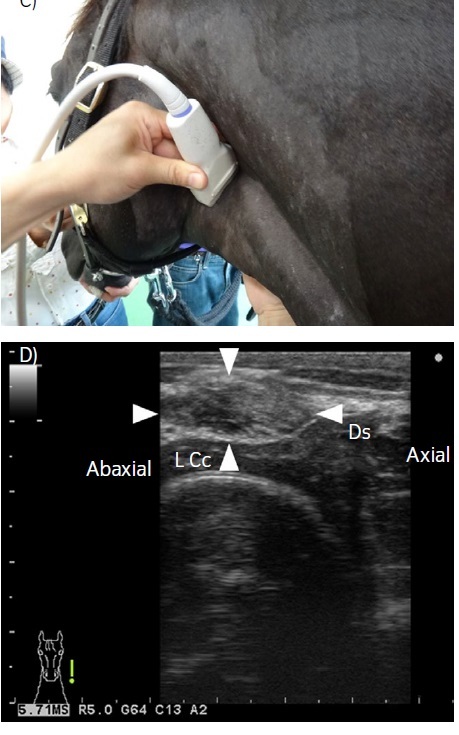

F I G U R E 1 An external longitudinal image visualising the three

cartilages, as the baseline image. Transducer position is shown in

(A) and the ultrasonographic image is shown in (B). Cranial (Cr) is to

the left and caudal (Cd) is to the right. Ac, arytenoid cartilage; Cc,

cricoid cartilage; Tc, thyroid cartilage